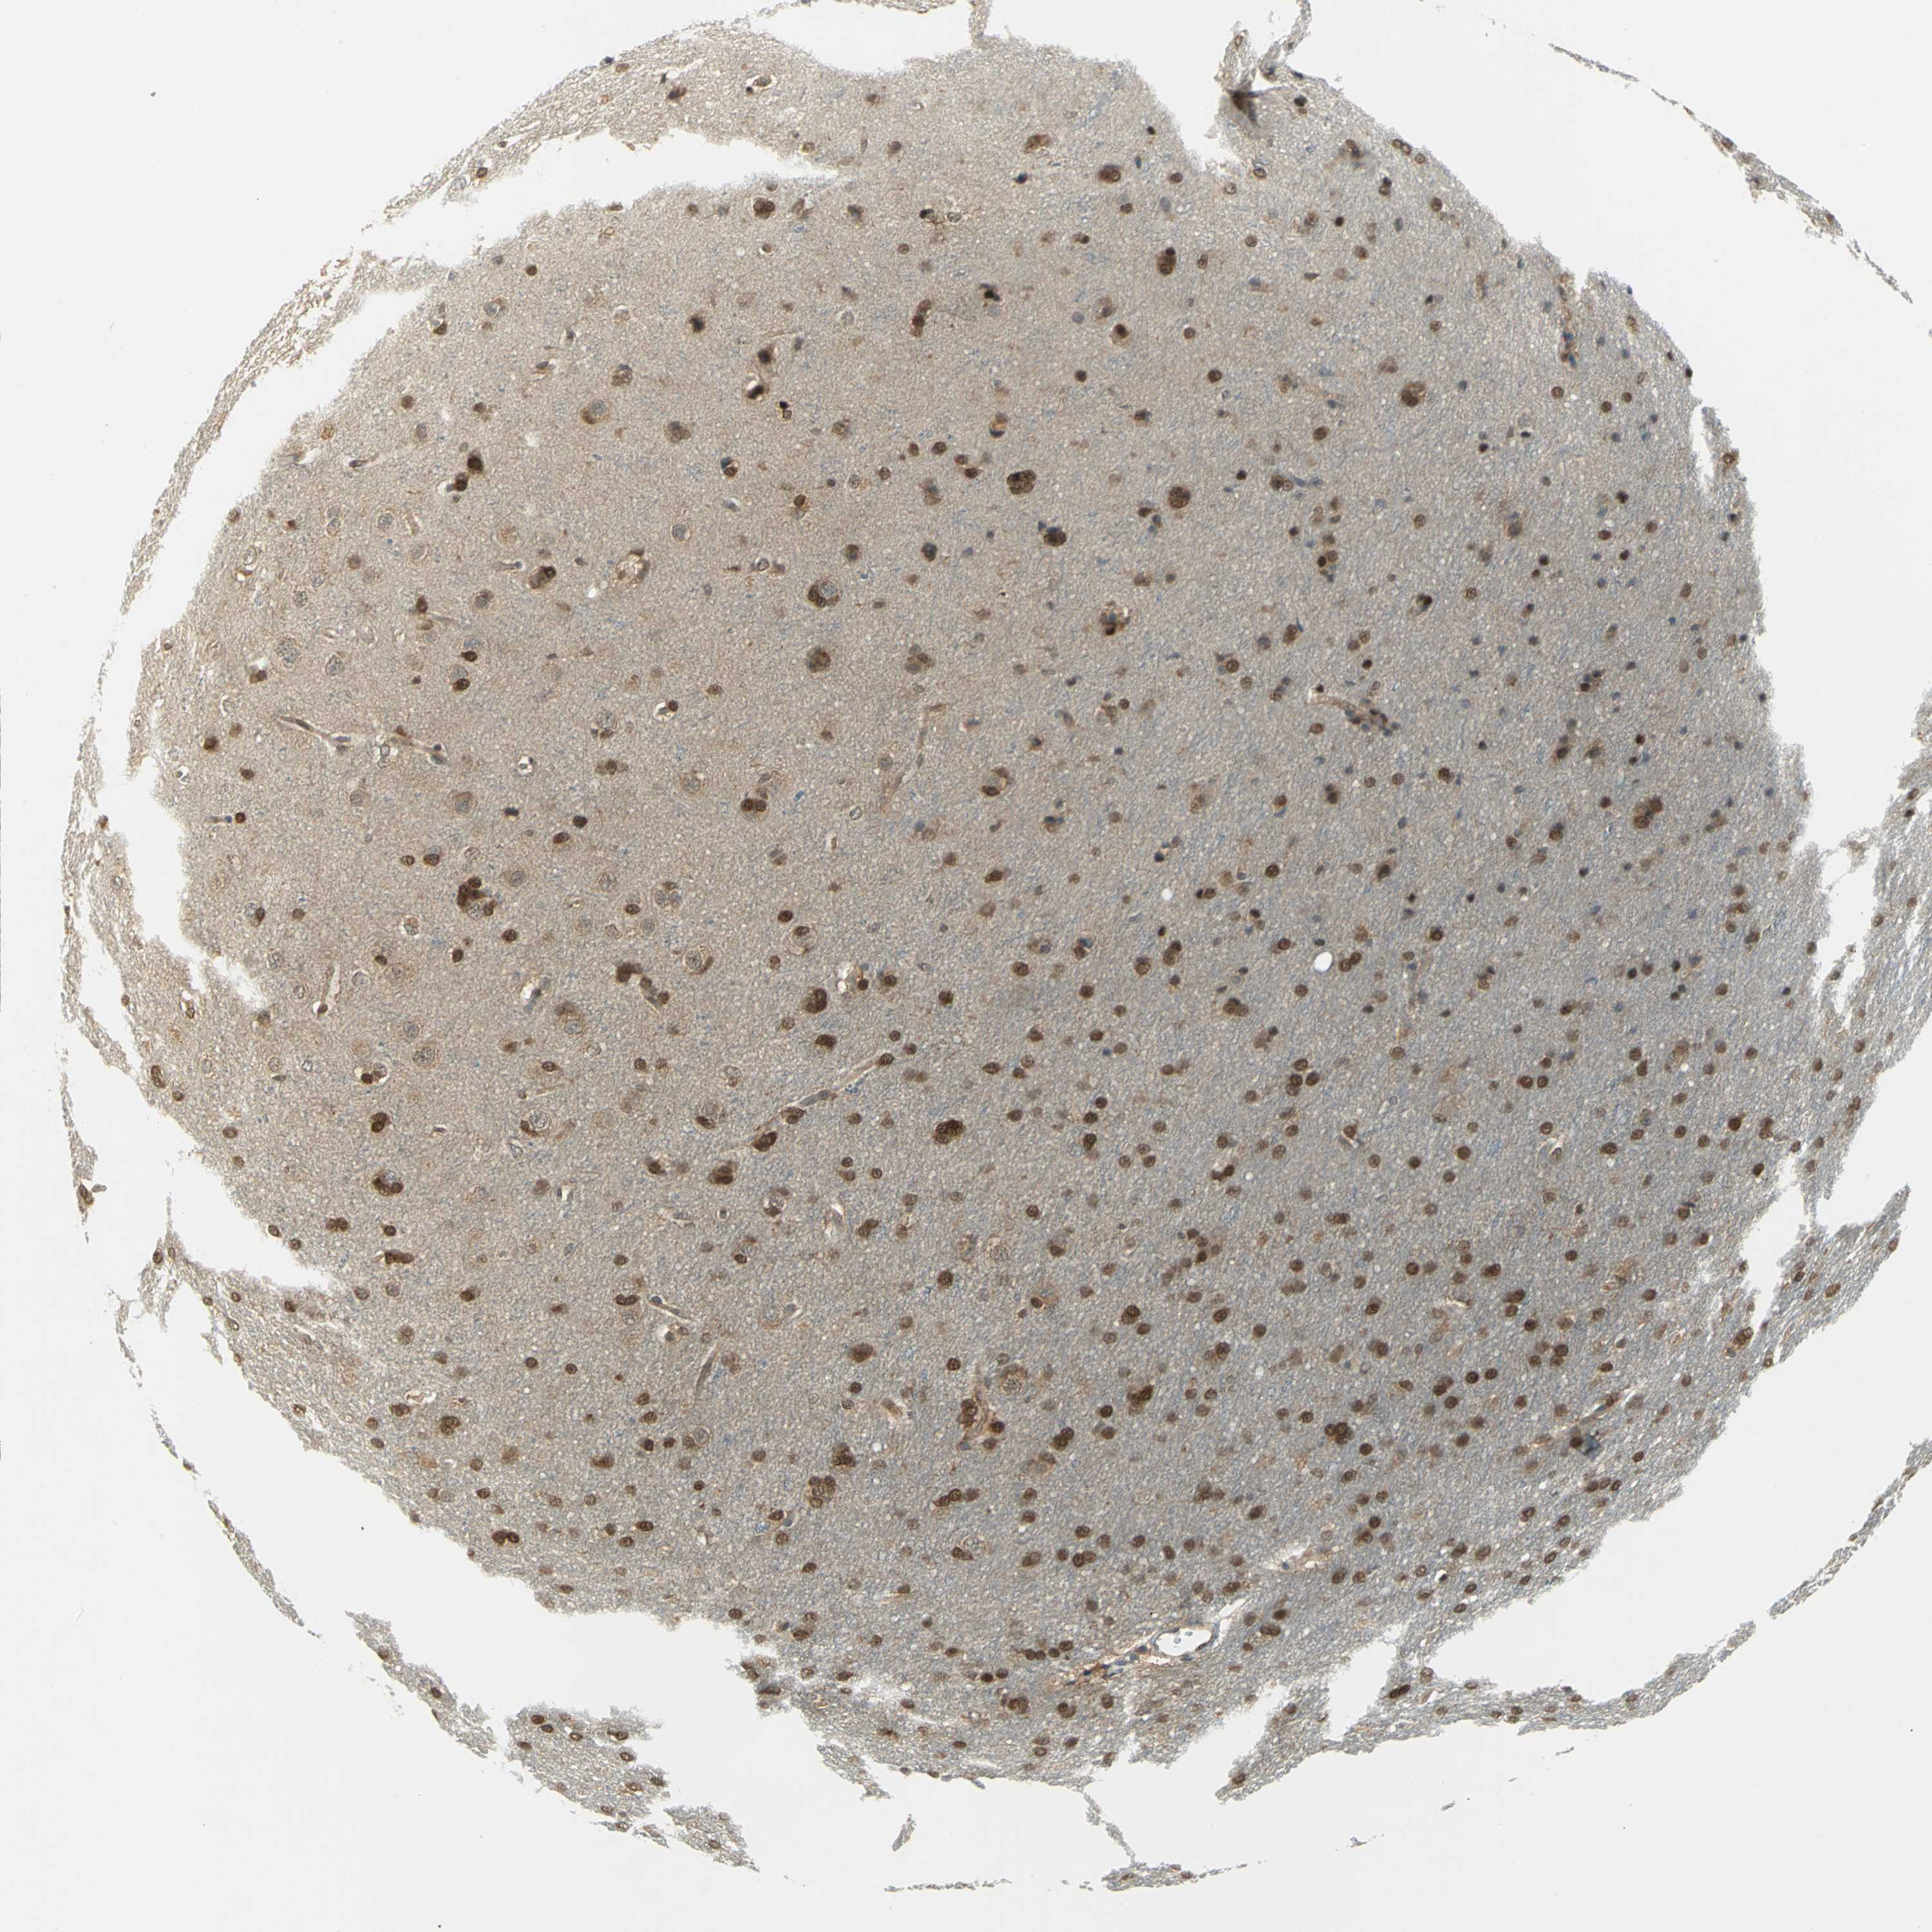

GLIOMA - Protein expressioni

A mouse-over function shows sample information and annotation data. Click on an image to view it in a full screen mode. Samples can be filtered based on level of antibody staining by selecting one or several of the following categories: high, medium, low and not detected. The assay and annotation is described here.

Note that samples used for immunohistochemistry by the Human Protein Atlas do not correspond to samples in the TCGA dataset.

Antibody stainingi

Antibody staining in the annotated cell types in the current human tissue is reported as not detected, low, medium, or high, based on conventional immunohistochemistry profiling in selected tissues. This score is based on the combination of the staining intensity and fraction of stained cells.

Each image is clickable and will lead to virtual microscopy that enables deeper exploration of all samples and also displays staining intensity scores, fraction scores and subcellular localization as well as patient and tissue information for each sample.

Antibody HPA023887

Antibody CAB005034

Antibody CAB018387

Staining

High

Medium

Low

Not detected

Intensity

Strong

Moderate

Weak

Negative

Quantity

>75%

75%-25%

<25%

None

Location

Nuclear

Cytoplasmic/membranous

Cytoplasmic/membranous,nuclear

Glioma, malignant, High grade

Glioma, malignant, Low grade

Glioma, malignant, NOS